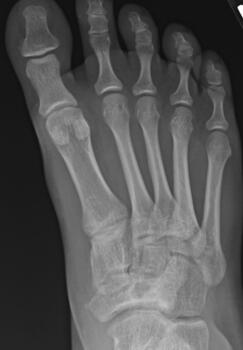

Here is a typical case presentation. A 21-year-old Marine at Ft. Leonard Wood for training underwent a Cincinnati release at one year old and had stellar follow-up. Her surgeon even wrote her medical waiver for entrance into the Marines. She ran track in high school. She finished boot camp and completed all of her Marine training, but now has chronic pain. She no longer can run. She hasn’t passed her physical training in over a year. She developed talonavicular DJD. By all accounts, her overall clubfoot should be rated an A+; no residual deformity, normal talocalcaneal angles on AP and lateral views, no equinus, no residual varus, only slight met primus elevatus, but no signs of a flattop talus. Clinically, she lacks subtalar range of motion, which I commonly find post-clubfoot release of any kind. So many in the military do very well for a while, but the demands of the military eventually catch up to them. We all root for clubfeet to make it, but the odds are stacked against them.